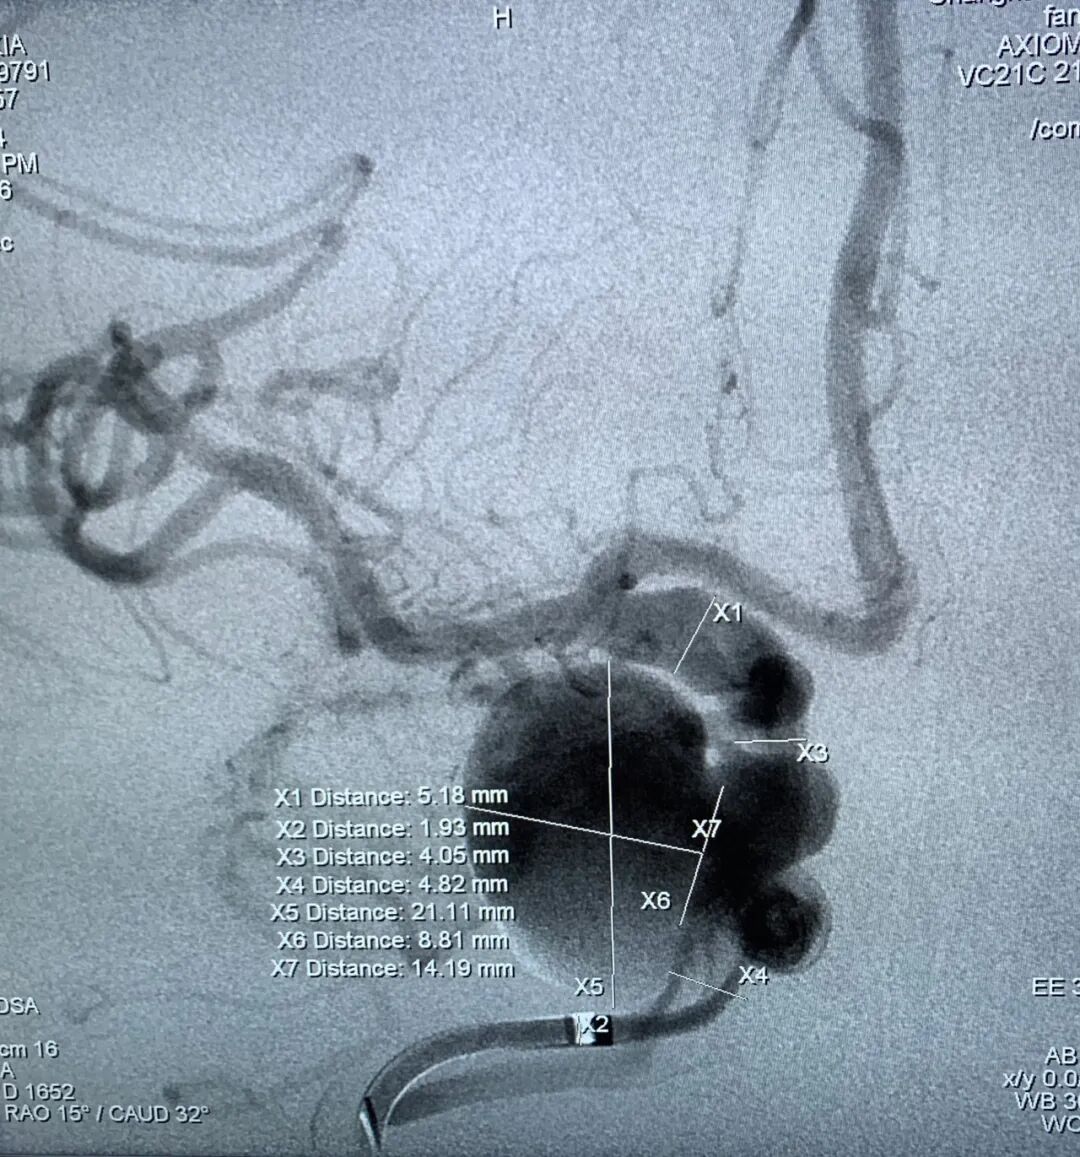

诊断结果:右侧颈内动脉床突段可见两枚囊状动脉瘤,动脉瘤大小分别为23*19mm、8.6*5.4mm。手术计划方案:右侧颈内动脉床突段动脉瘤抗凝血流导向密网支架植入术。

1、以Seldinger技术穿刺右侧股动脉成功后,留置6F股动脉鞘。6F DA导管超选至右侧颈内动脉海绵窦段,行3D造影提示:右侧颈内动脉床突段分叶状动脉瘤,载瘤动脉无严重迂曲,未见合并载瘤动脉严重狭窄,未见严重的脑血管痉挛。2、选择最佳工作角度,路图下用微导丝辅助支架0.027"微导管超选至右侧大脑中动脉,通过支架微导管释放一枚5.0*35mm抗凝血流导向密网支架(纽创医疗)。3、抗凝血流导向密网支架放置合适位置,完全覆盖瘤颈,释放后抗凝血流导向密网支架打开良好。术后造影见动脉瘤瘤体造影剂滞留明显,动脉瘤瘤颈造影剂滞留明显,靶动脉瘤Raymond Ⅲ级。